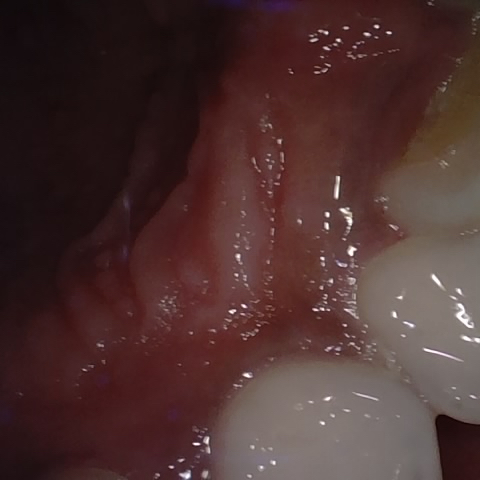

Annotated as "Good"